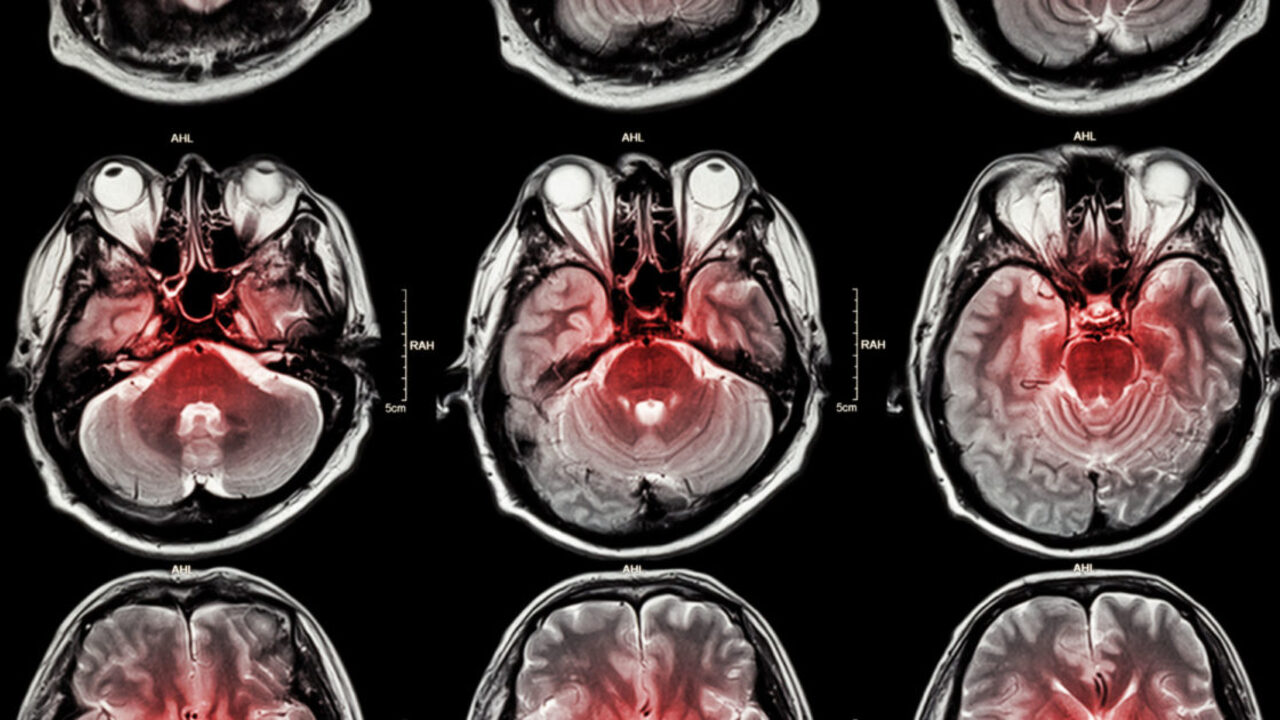

The risk of stroke increased as TYG-GIVE-GİRE increased. After all factors have been taken into consideration, the growth of TYG-WWI indicators was associated with an increase of 15%of the possibility of a stroke.

The researchers also divided all participants into four groups depending on the TYG-Second World-WWI values. The risk of stroke was higher than the group with the lowest parameters in other groups: 38% and the second largest TYG-WWI value compared to people with the highest rates and 37% compared to those with the largest TYG-WWI. At the same time, the dependence was linear: the risk of stroke increased as TYG-Second Earth-Verses increased.

Interestingly, this tendency was expressed in young people and humans without coronary heart disease, and gender, ethnicity, education, cigarettes and alcohol use had no significant impact on this addiction.